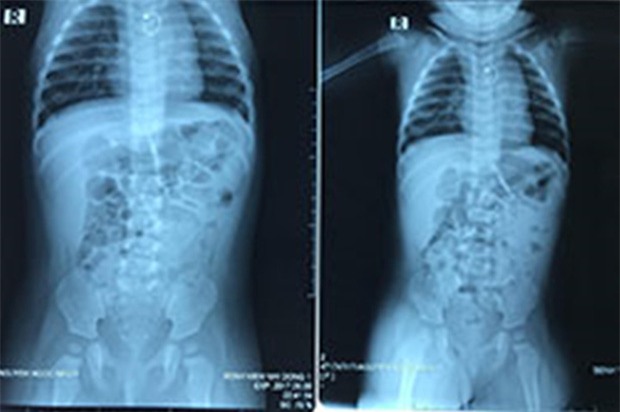

Qua thăm khám và chụp X-quang, các BS nhận định dị vật cản quang nằm trong thực quản đoạn ngực. Dị vật hình chiếc hoa tai có 1 đầu nhọn nguy cơ trầy, rách thực quản cao khi can thiệp thủ thuật lấy dị vật.